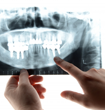

急な虫歯の痛み・義歯や入れ歯のトラブル・歯茎の腫れ